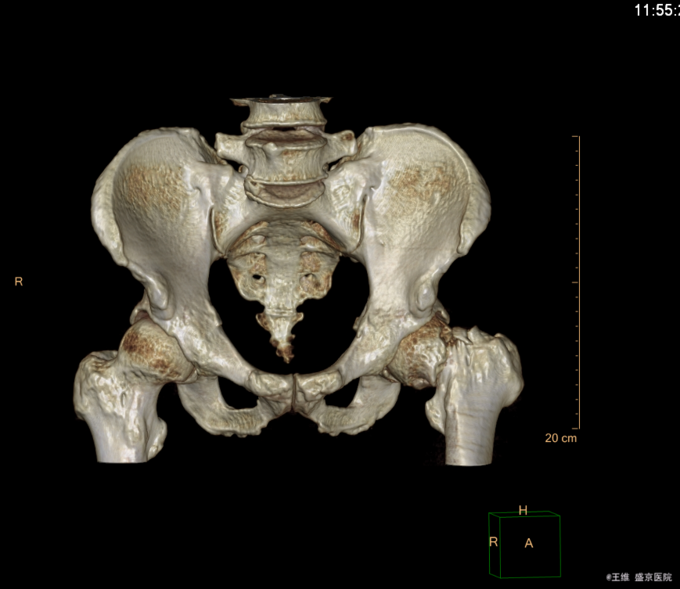

患者自述于2015-12-3日15时在工厂干活时不慎由梯子上摔落(高约3米),致左髋部疼痛、活动受限,不能站立行走,急送至当地医院行骨盆DR示:左股骨颈骨折。现患者为求进一步诊治来我院,急诊以“左股骨颈骨折”为诊断收入我科。患者自受伤以来一般状态可,无发热,无头晕、呕吐,无胸闷、心悸呼吸困难,无腹痛、腹泻,饮食可,睡眠可,二便正常。

专科查体:患者平车入病房,左小腿胫骨牵引中,右下肢外展、外旋约45度,患肢缩短约1cm 右髋部疼痛,压痛(+),右下肢感觉未见异常,活动可,双侧足背动脉搏动可触及。

患者入院后完善相关检查,查无明显手术禁忌症后,CSEA下行左股骨颈骨折闭合复位空心钉内固定术,术后患者抗炎等对症治疗,患者第二天退院。嘱患者卧床休息3个月后,复查。